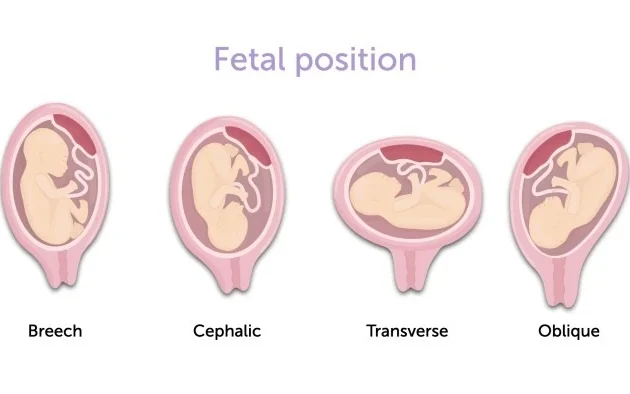

Final/Position Scan

Doppler Scan